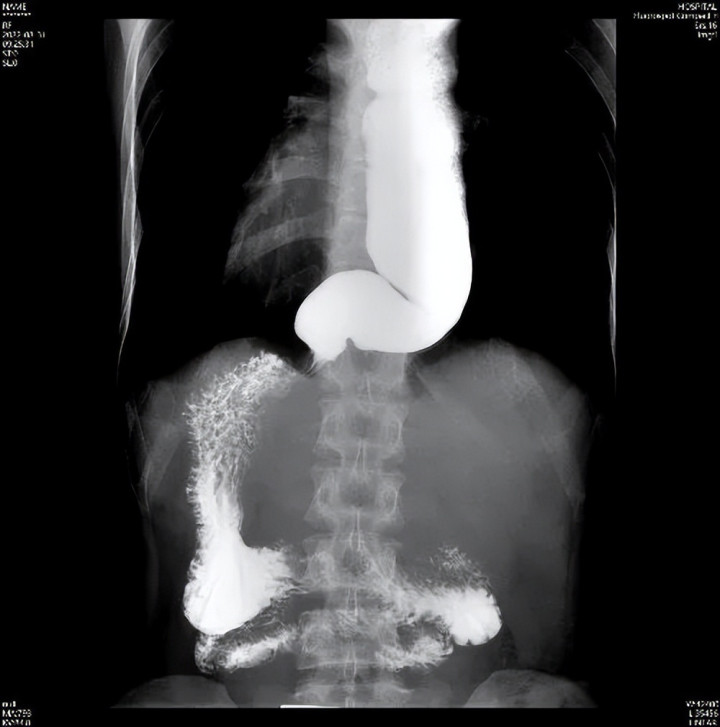

2.食管钡剂造影

给食管拍“动态 X 光”,你需要喝一种白色的钡剂(像牛奶一样的液体),然后在 X 光下观察它通过食管的过程。贲门失弛缓症患者的贲门部位会出现典型的“鸟嘴样”狭窄——食管末端像鸟嘴一样收紧,上面的食管却明显扩张,还能看到钡剂在食管里“慢慢悠悠下不去”。

钡餐造影:食管却明显扩张扭曲,贲门门部位 “鸟嘴样”狭窄,钡剂下去慢慢悠悠。